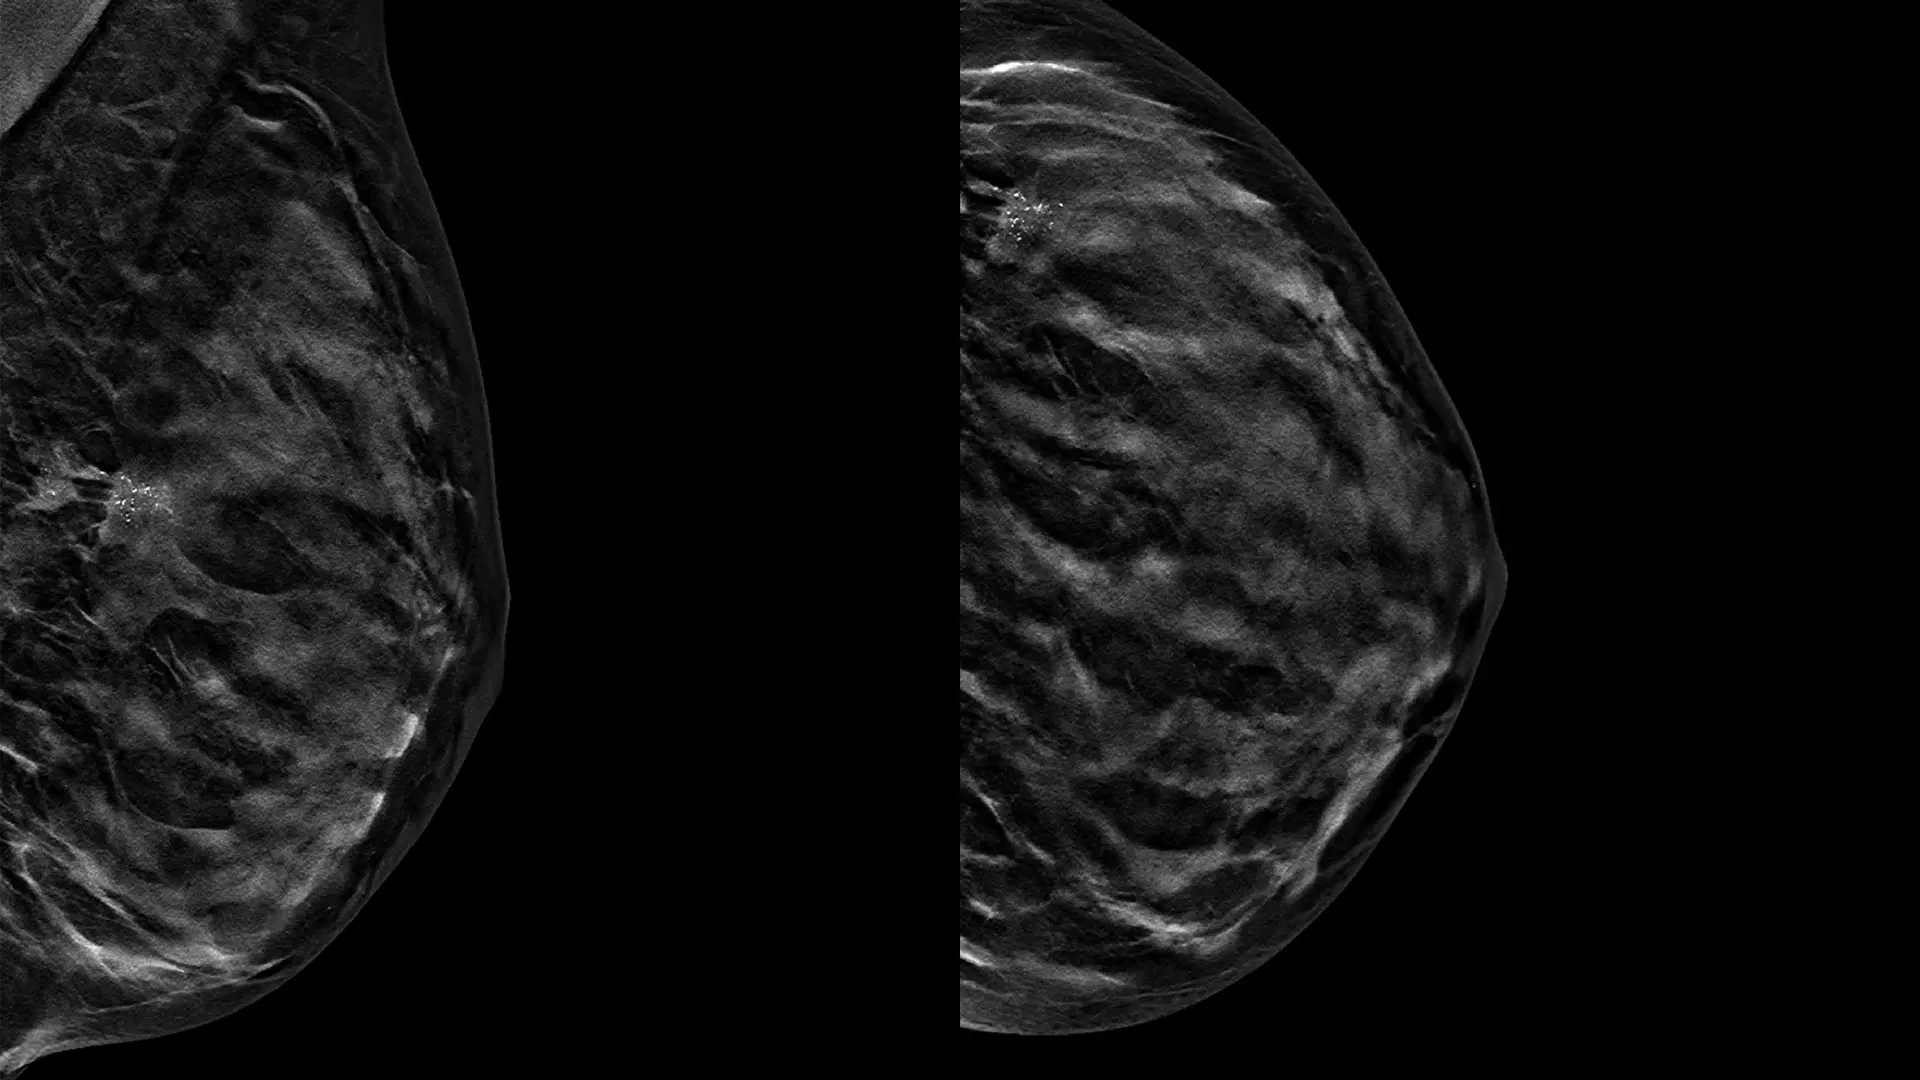

Il Prof. Alejandro Martín Sanchez entra nel Gruppo USI: nuovo riferimento di eccellenza per la chirurgia senologica a Roma

Il Gruppo USI rafforza il proprio impegno nella prevenzione, diagnosi e cura delle patologie...